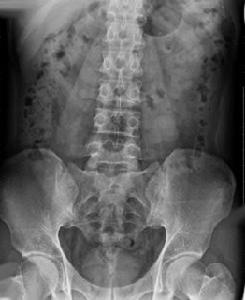

2.X線檢查

早期脊椎周圍關節突出,骶髂關節間隙模糊;中期脊椎活動受限強直,骶髂關節蠶蝕樣改變,部分韌帶骨質破壞,方椎小關節間隙模糊;晚期骶髂關節融合,脊柱呈竹節樣變,脊椎強直駝背,呈竹節樣變。